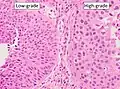

The 1973 WHO grading system for transitional cell carcinomas (papilloma, G1, G2 or G3) is most commonly used despite being superseded by the 2004 WHO[14] grading for papillary types (papillary neoplasm of low malignant potential [PNLMP], low grade, and high grade papillary carcinoma). High-grade carcinoma typically displays more pleomorphism, multiple mitoses, euchromatin and relatively prominent nucleoli, and uneven distribution of nuclei.

Transitional cell carcinoma, being low-grade to the left, and high-grade to the right. H&E stain

Transitional cell carcinoma, being low-grade to the left, and high-grade to the right. H&E stain -